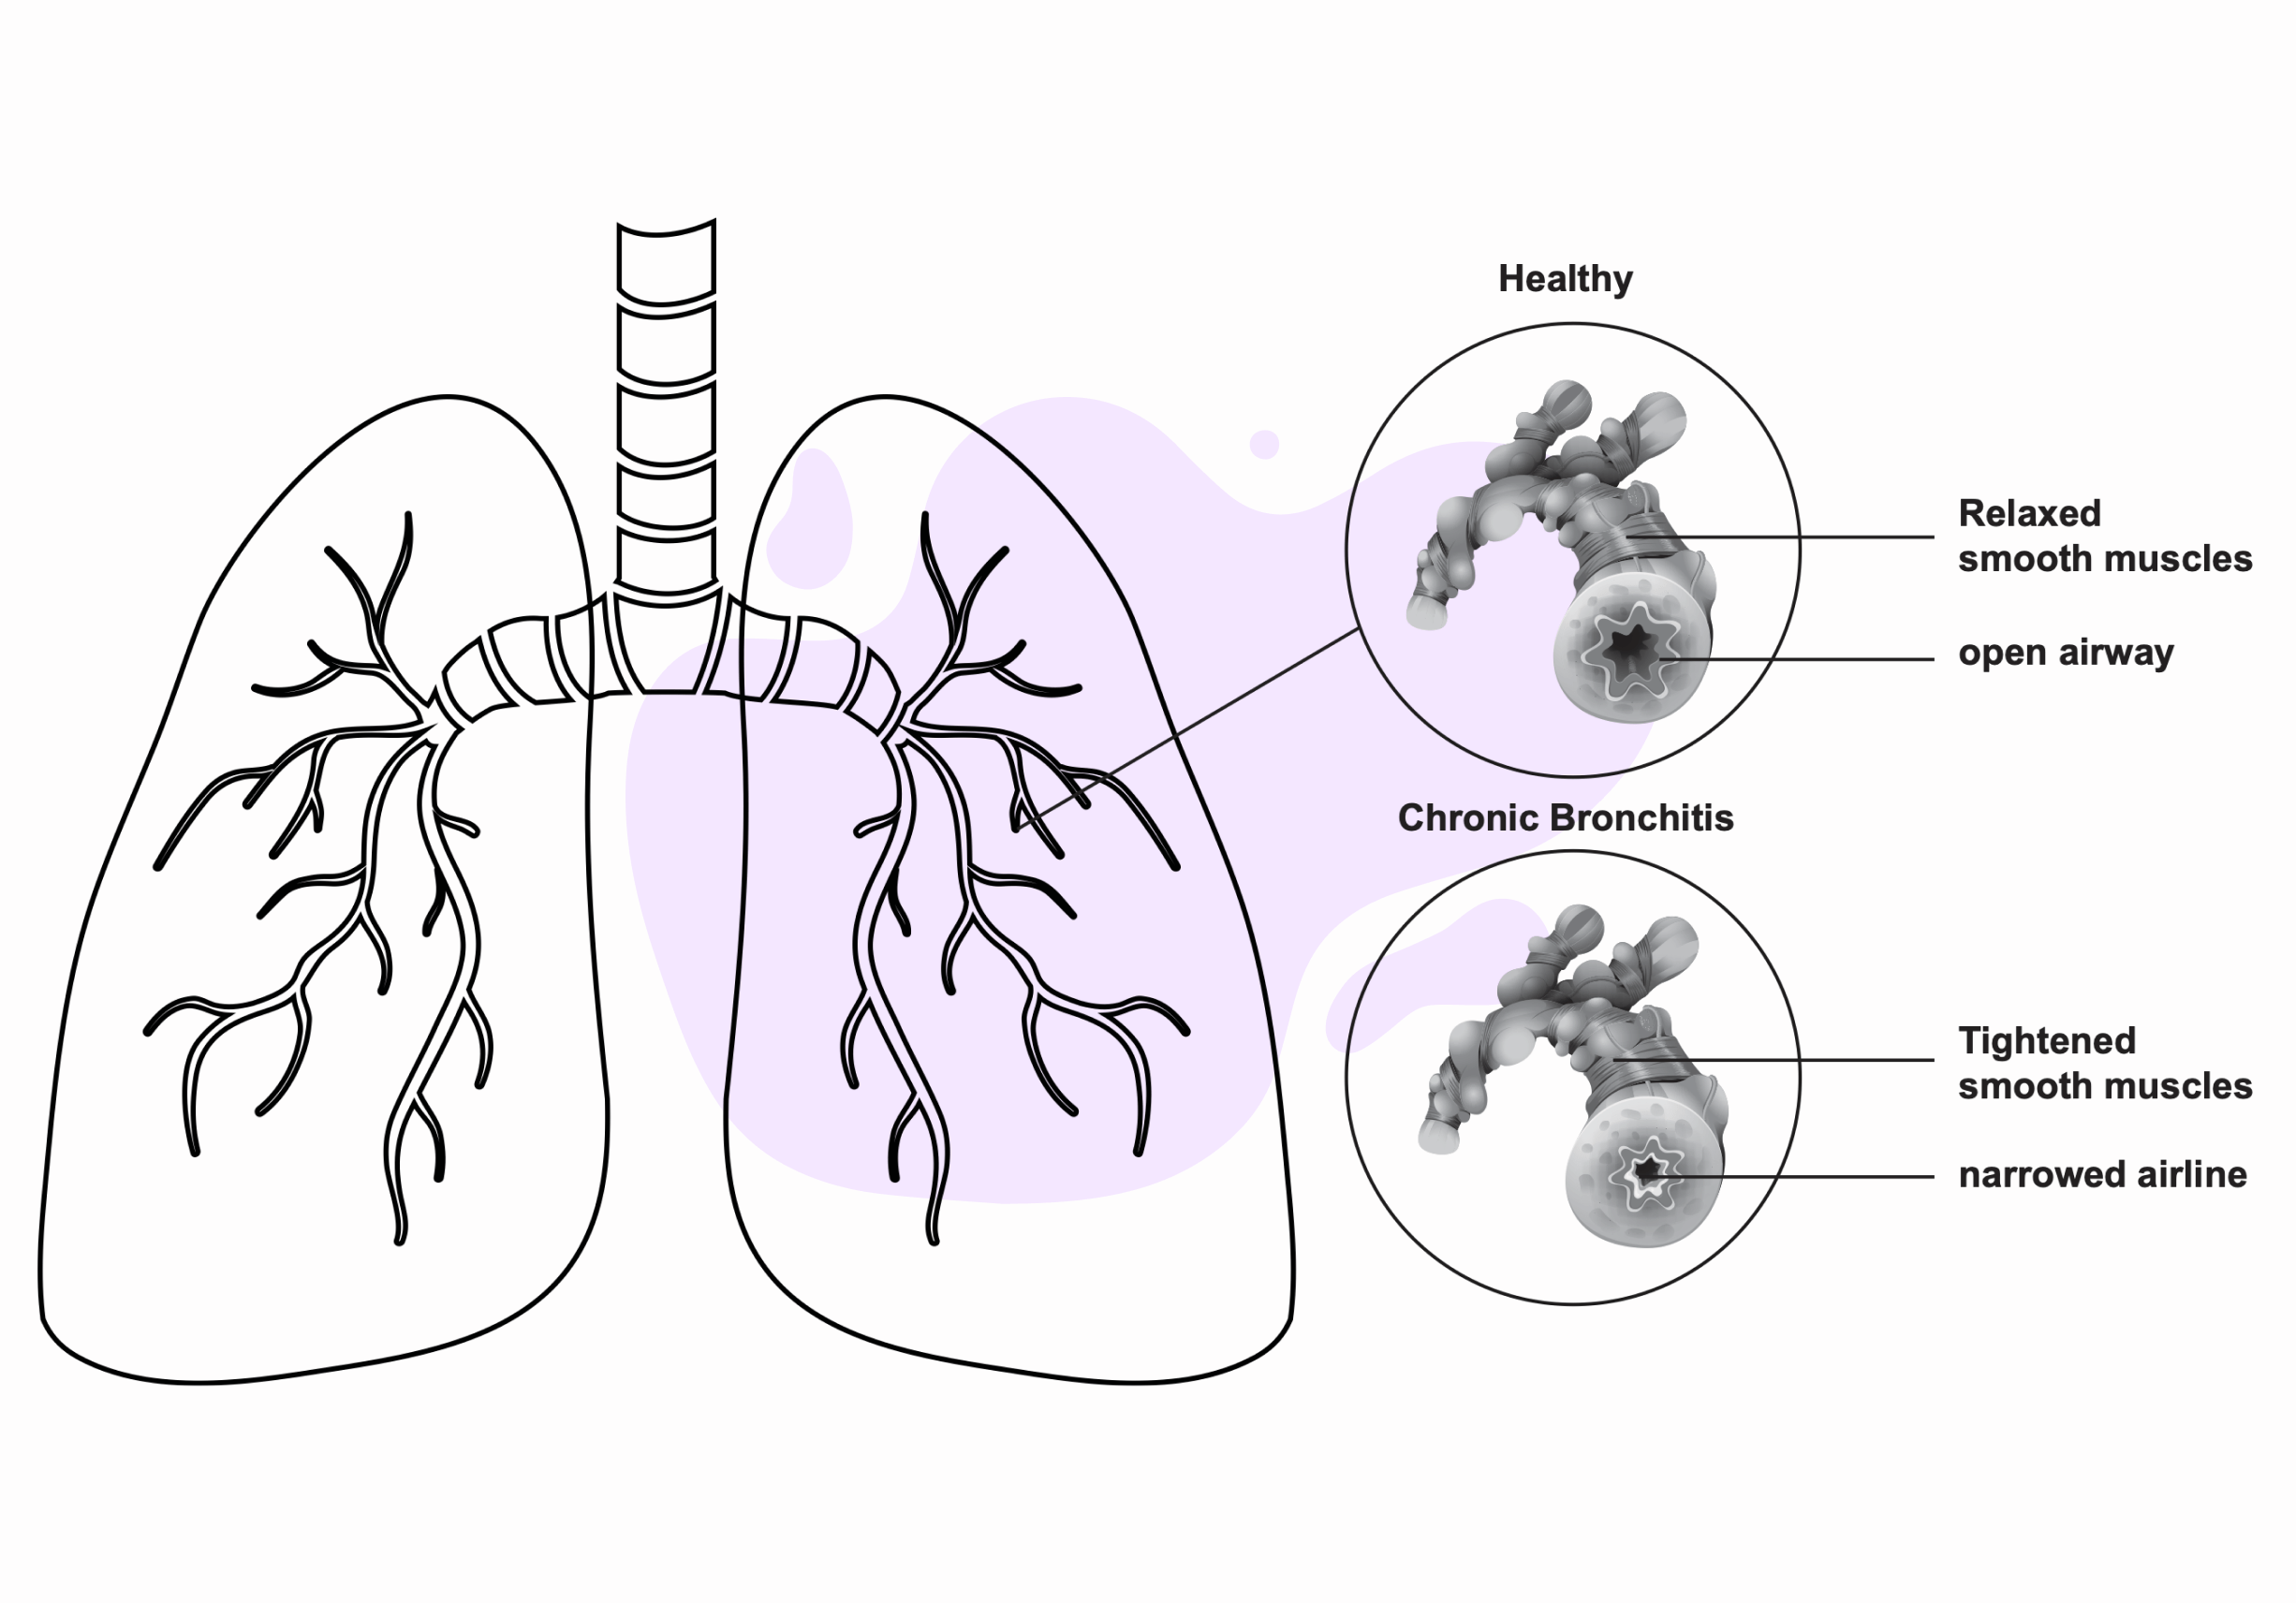

1. Respiratory tract irritation

1. Respiratory tract irritation

Ozone exposure can cause airway constriction. As causing air to become trapped in the alveoli and irritating the respiratory tract.

5. Reduced lung function

Ozone exposure constricts the airways. And it obstructiveness restricts the lungs from functioning normally, reducing lung function.